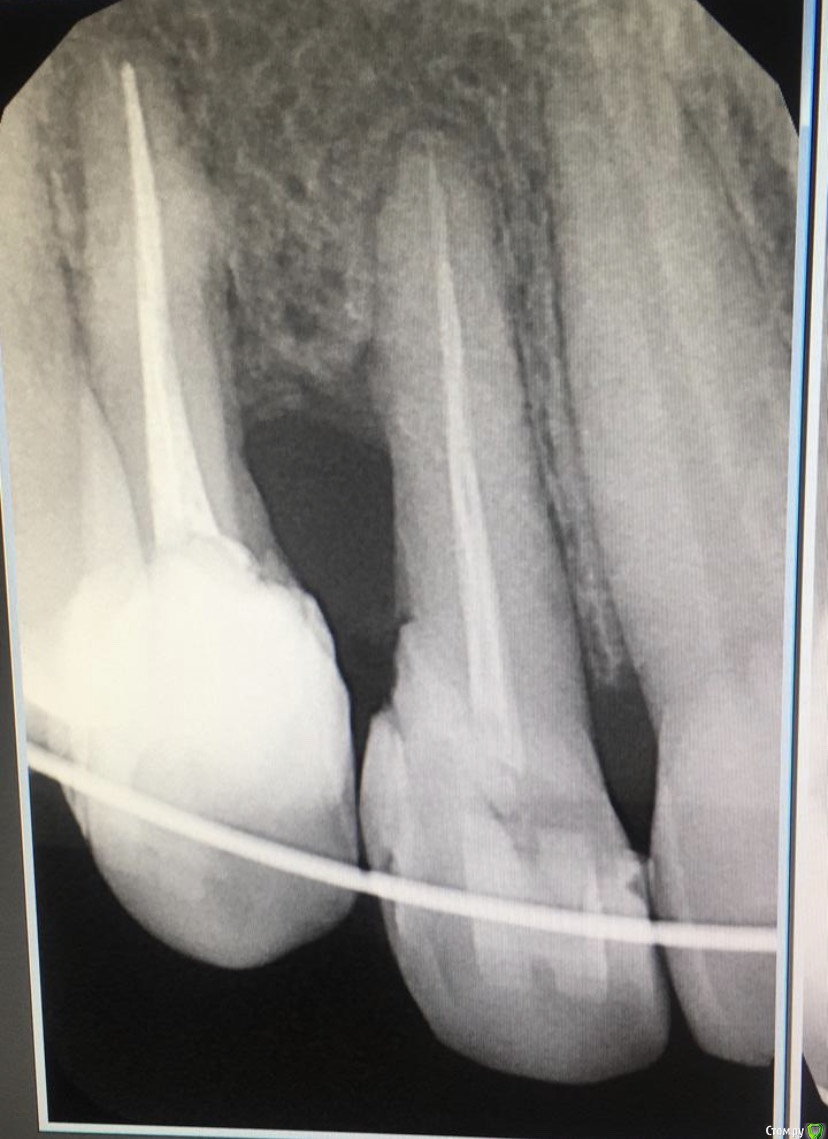

It'sGeorgy Опубликовано 4 июля, 2020 Поделиться Опубликовано 4 июля, 2020 Доброго времени суток!История такая: девушке (примерно 30-35 лет) в детстве был удален клык. После чего она перенесла 2 неудачных ортодонтии. Сейчас находится в процессе 3ьей попытки ортодонтического лечения. Пол года назад ситуация была такая: Сейчас такая: Котэ сделает в теч недели, прикреплю сюда же. Перкуссия 1.2 и 1.4 безболезненна. 1.4 без подвижности, 1.2 с I степенью подвижности. Само собой, как только снимут брекеты подвижность увеличится.Из личных мыслей: попробовать открыть, откюретажить корни, Эмдогейн, большой ССТ с бугра. Жду от этого небольшого прироста кости и "закрытия" кармана, чтобы внутрь перестала попадать пища.Всегда актуальный вариант: удаление обоих, мостовидная конструкция 1.1-1.5. Буду рад любым советам. Ссылка на комментарий

annda Опубликовано 4 июля, 2020 Поделиться Опубликовано 4 июля, 2020 (изменено) ИМХО, проблема в травматической окклюзии. Зубы выколачиваются нижней челюстью. Нет клыка, они работают за клык, да еще и депульпированы, да еще и недоразвитие верхней челюсти с этой стороны. Они просто не вывозят такую нагрузку, кость уходит и будет уходить.Надо расширять место под клык и ставить там имплантат , по идее.Тогда будет шанс. Иначе зубы уйдут.Банально поставьте палец в проекцию корня двойки и попросите постучать. Ощутите вибрацию.И все поймете.А потом в латеротрузии движения посмотрите, по кому ходят нижние зубы, по кому идет нагрузка с этой стороны. И тоже все поймете. Изменено 4 июля, 2020 пользователем annda 3 Ссылка на комментарий

It'sGeorgy Опубликовано 10 июля, 2020 Автор Поделиться Опубликовано 10 июля, 2020 ИМХО, проблема в травматической окклюзии. Зубы выколачиваются нижней челюстью. Нет клыка, они работают за клык, да еще и депульпированы, да еще и недоразвитие верхней челюсти с этой стороны. Они просто не вывозят такую нагрузку, кость уходит и будет уходить.Надо расширять место под клык и ставить там имплантат , по идее.Тогда будет шанс. Иначе зубы уйдут.Банально поставьте палец в проекцию корня двойки и попросите постучать. Ощутите вибрацию.И все поймете.А потом в латеротрузии движения посмотрите, по кому ходят нижние зубы, по кому идет нагрузка с этой стороны. И тоже все поймете.По итогу, все было именно так, как вы сказали. Самое досадное, что у пациентки в принципе сейчас смыкается только 6 центральных зубов сверху и 6 центральных снизу. Отправил обратно к ортодонтам, пусть решают вопрос. Всем ещё раз большое спасибо. Если не забуду, расскажу потом чем история закончилась. Ссылка на комментарий